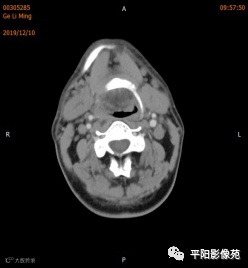

双侧颌下腺、腮腺对称,形态完整,右侧颌下腺强化程度较左侧略低,其内涎腺管增粗,周围脂肪间隙清晰,邻近骨质未见异常,右侧涎腺走行区可见结节样致密影,较大者大小约0.5cm,双侧颌下软组织对称,未见异常密度,所扫范围颈部未见明显肿大淋巴结。

考虑右侧涎腺管结石。

右侧颌下腺强化程度较左侧略低,涎腺管扩张,考虑炎性改变,请结合临床。